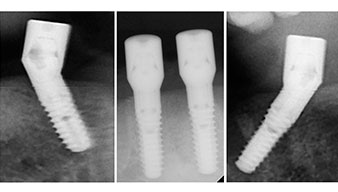

A three-dimensional cone beam computed tomography scan (CBCT, Planmeca) was performed to aid planning and minimize risks. This revealed that the quality and quantity of the available bone were sufficient for the surgery and immediate restoration using the Fast & Fixed method. Following the protocol for this concept, the implants are inserted at 35, 32, 42 and 45. Angling the distal implants by up to 45° shifts the emergence profile to posterior and generates a larger support polygon (Fig. 3).

Angled abutments (35°) were screwed in to compensate for the divergence of the distal implants, with the result that the emergence profile of all implants was as perpendicular as possible to the bite plane. This is a prerequisite for occlusal placement of the provisional and subsequently the permanent denture (Fig. 15 and 16).